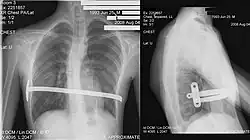

| Exemplo de caso severo. | |

Pectus Excavatum é uma deformidade do tórax e osso esterno caracterizada por uma depressão do esterno e costelas na frente do tórax. O grau de severidade varia muito. A anomalia é conhecida entre os leigos como "peito de sapateiro", "peito escavado", "tórax escavado", entre outros.[1]